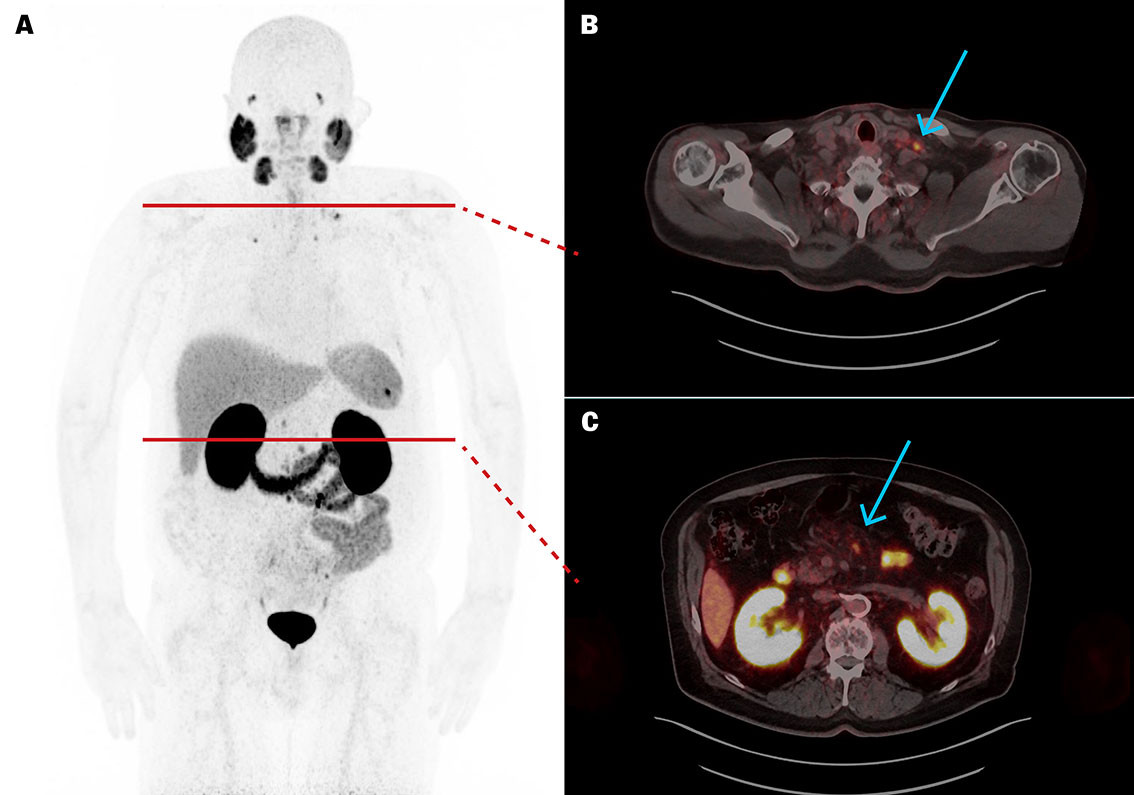

PSA in plasma (p-PSA, reference range 0–4.0 µg/L for men ≥ 60 years) was 154 µg/L and the PSA doubling time was 4.5 months. PET/CT with the Gallium-68-labelled radiopharmaceutical tracer prostate-specific membrane antigen radioligand (PSMA-RL) ([⁶⁸Ga]PSMA-11) revealed high uptake in scattered metastatic lymph nodes in the pelvis, abdomen, chest and neck, as well as a solitary bone metastasis in the right clavicle (Figure 1). The uptake indicated possible suitability for treatment with Lutetium-177 (a beta-emitting radionuclide) PSMA radioligand therapy ([¹⁷⁷Lu]PSMA-RL).

Five weeks after the fifth course of treatment, p-PSA was 1.8 µg/L. [⁶⁸Ga]PSMA-11 PET/CT revealed a significant reduction in the size of metastases (Figure 2), with the largest (target lesion) decreasing in diameter from 10 to 4 mm. Apart from decreased appetite and constipation, the treatment was well tolerated without affecting renal, salivary gland or bone marrow function.

Seven months after the fifth treatment, p-PSA had risen to 14.3 µg/L and [⁶⁸Ga]PSMA-11 PET/CT revealed new small skeletal metastases with high uptake, while lymph node metastases remained unchanged. The treatment thus had a good but temporary therapeutic effect on the metastases.